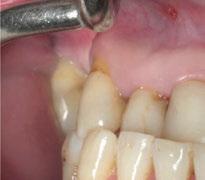

Para ilustrar el proceso, presentamos el caso de una mujer joven diagnosticada de carcinoma adenoide quístico en la región posterior del hemipaladar izquierdo (Figuras 1 y 2). El procedimiento quirúrgico realizado fue una

maxilectomía parcial que incluyó las piezas 24-26 y desde el reborde alveolar hasta la base del cráneo (Figuras 3 y 4). En este caso, la órbita y el globo ocular pudieron ser preservados. La reconstrucción inmediata se realizó mediante un colgajo de músculo temporal homolateral (Figura 5) y el defecto de la fosa temporal fue cubierto mediante una malla de titanio. Posteriormente, la paciente recibió radioterapia (Figuras 6 y 7). 2 años más tarde se diseñó un IS con anclaje en el arbotante nasomaxilar, zona subnasal izquierda

Figura 1. Imagen preoperatoria de la paciente.

Figura 2. Carcinoma adenoide quístico en región posterior del hemimaxilar izquierdo.

Figura 3. Maxilectomía parcial.

Figura 4. Defecto maxilar tras resección del tumor.